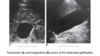

Sonographic Evaluation of the Biliary System

the main lobar fissure (MLF) is seen as an echogenic linear echo within the liver (L) connecting the right portal vein (PV) to the neck of the gallbladder (GB).

Main Lobar Fissure

-string connecting to PV; GB is the balloon; connects to GB neck

sag. GB

Trv. GB